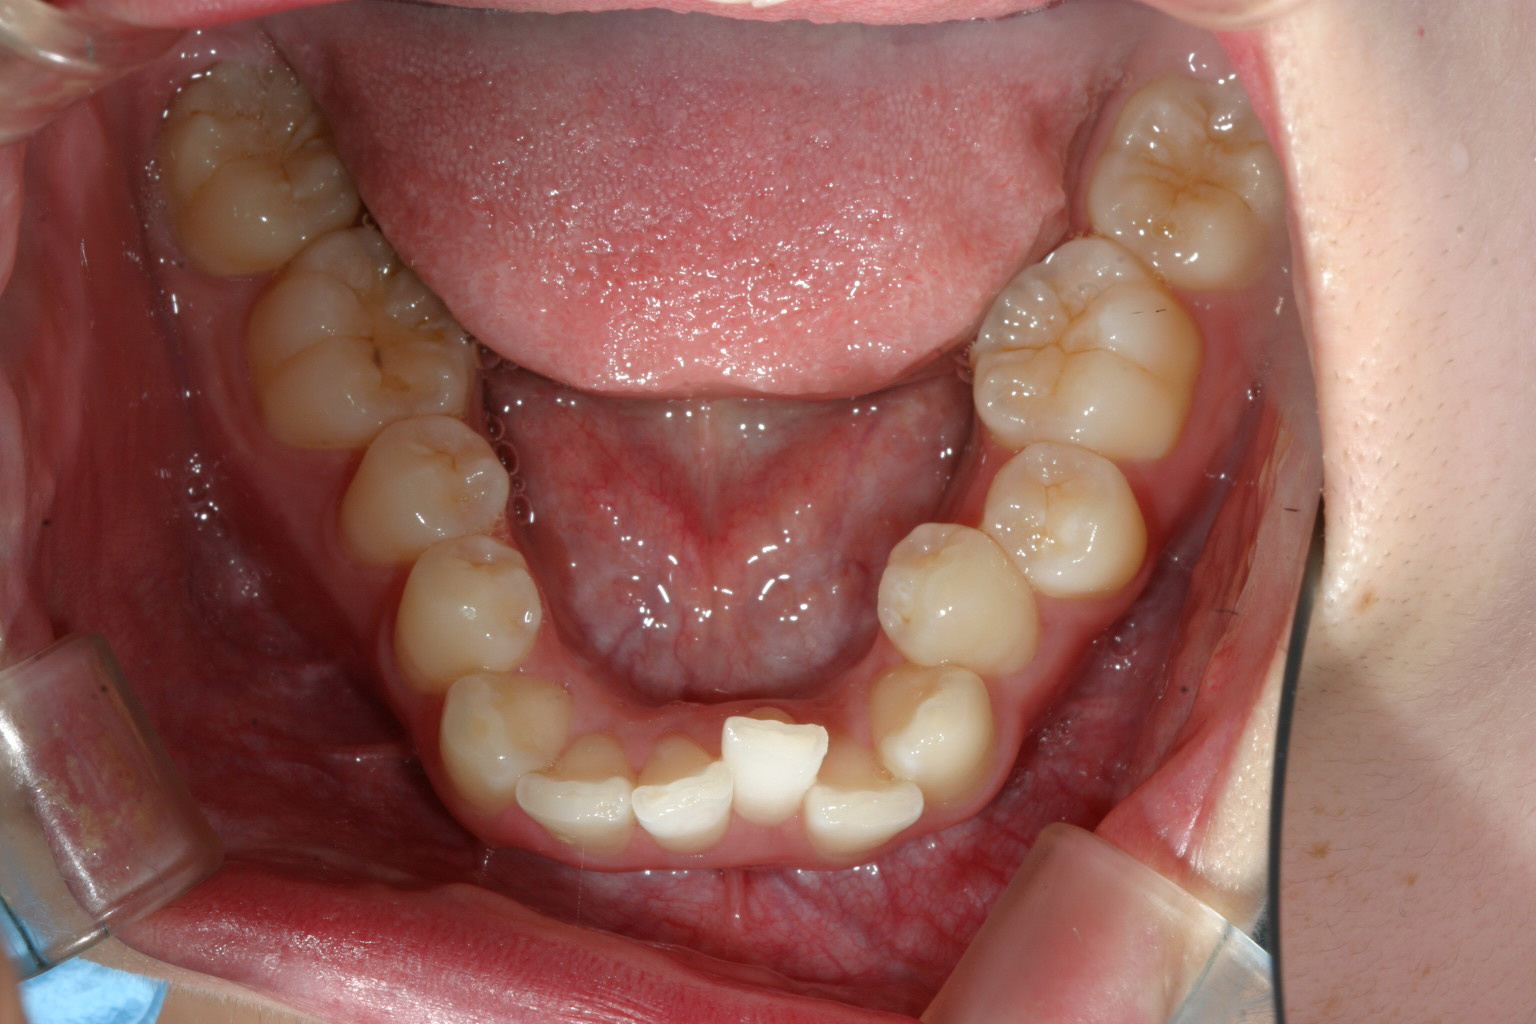

綺麗なアーチにしました。

下顎も綺麗なアーチにしないと噛めませんからね!

インビザラインのみで改善しました。この症例はインビザラインが日本に導入されて最初の頃の症例でその頃のインビザラインは思うように歯が動いてくれず苦労した症例です。

でもインビザラインでもこのように歯列の形態迄改善できるんだと感激させて頂きました。